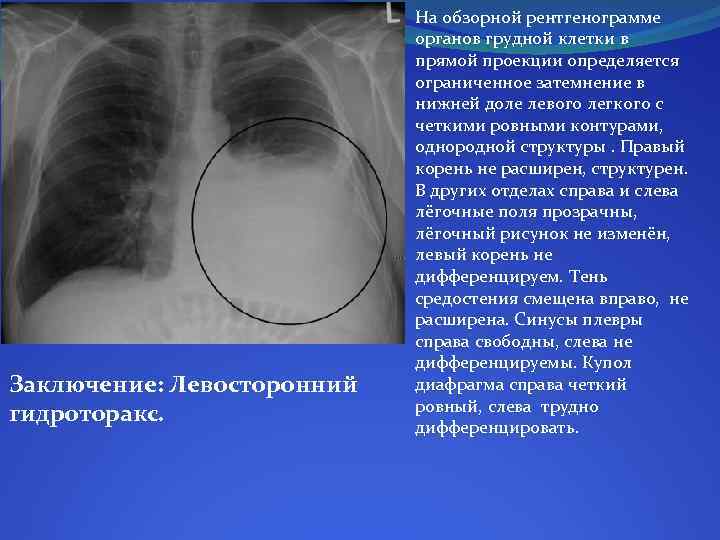

Рентгенологические изображения и синдромы патологии легких

Раздел: Кадры-подсказки